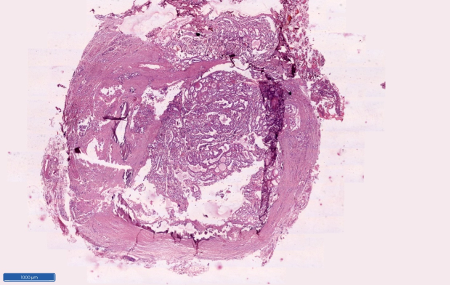

| Figure

1: Smears show only cyst macrophages and

think colloid (Haematoxylin and Eosin, x

100) |